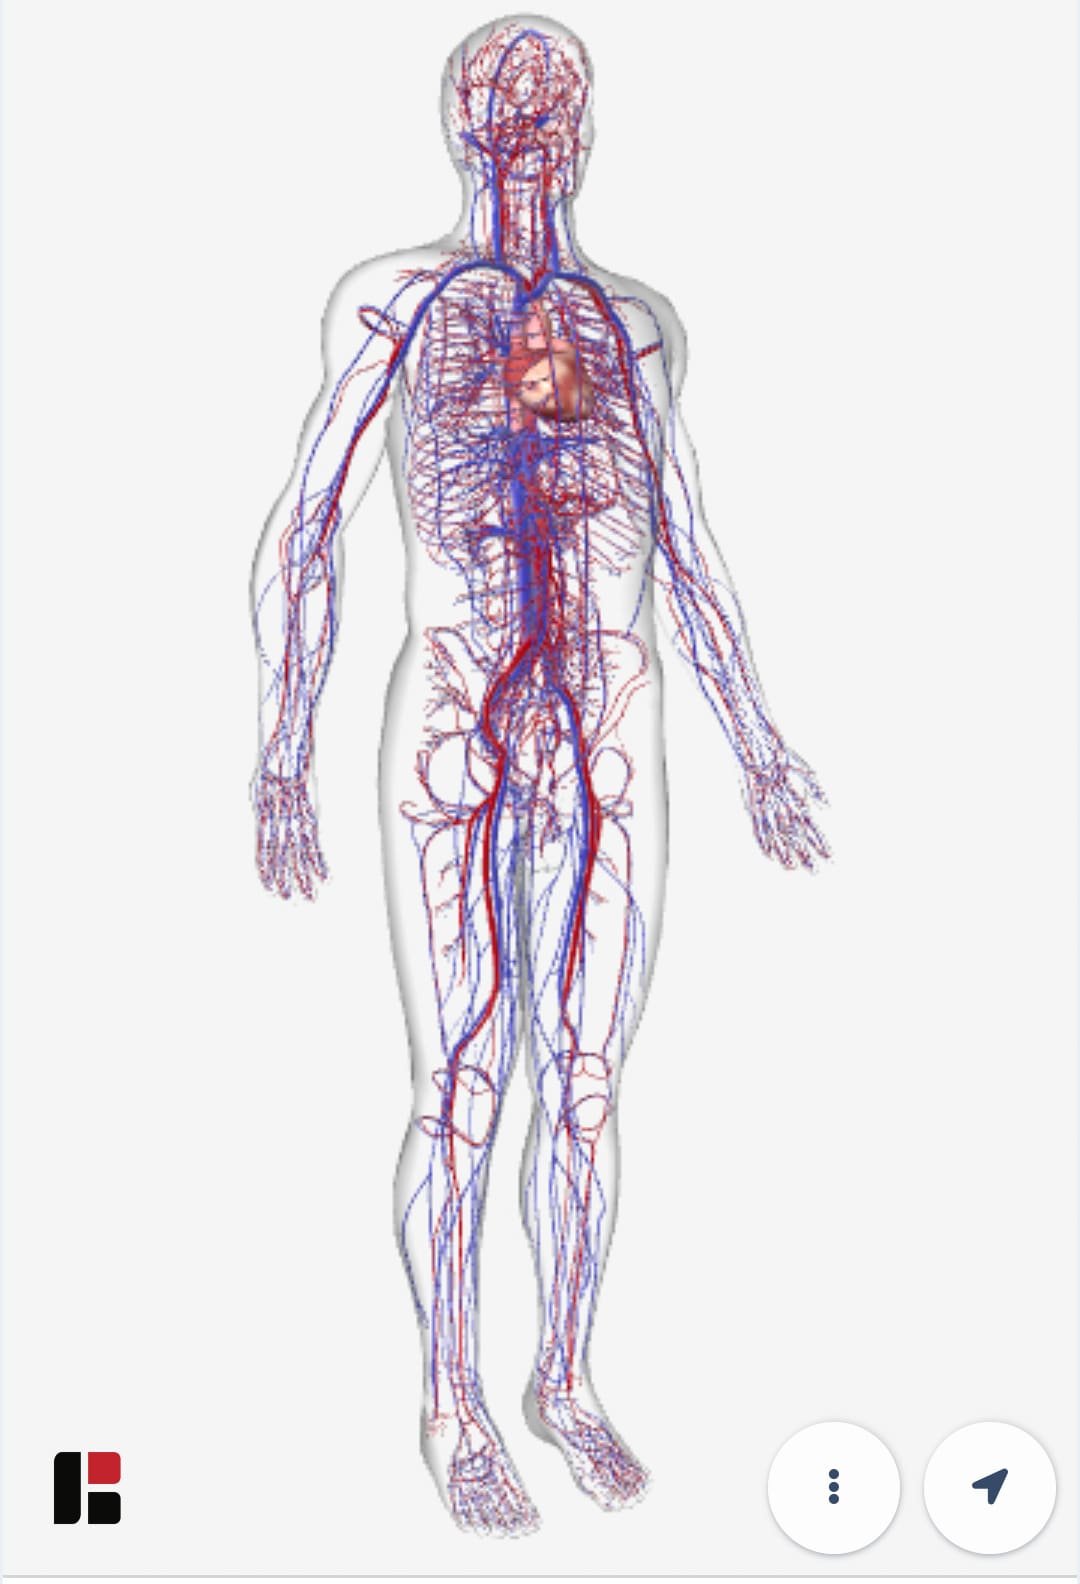

અલબત્ત, વાત ગૂગલ જેવી ટેક કપનીની હોય એટલે દેખીતું છે કે વાત માત્ર બે-ઘડીની રમતથી અટકે નહીં.ગૂગલે હવે આ રમત ઘણી વિસ્તારી છે. આ માટે બાયોડિજિટલ. () નામની એક કપનીની મદદ લેવામાં આવી છે. આ કપનીએ મેડિકલ પ્રોફેશનલ્સ અને સ્ટુડન્ટ્સ માટે એક સોશિયલ મીડિયા પ્લેટફોર્મ જેવી વ્યવસ્થા વિક્સાવી છે. તેણે એક ઇન્ટરઅક્ટિવ ૩ડી સોફ્ટવેર પ્લેટફોર્મ વિક્સાવ્યું છે, જેની મદદથી હ્યુમન એનેટોમી એટલે કે માનવશરીરની સંપૂર્ણ રચના, તેનાં વિવધ અવયવતંત્રો વગેરે જાેઈ-સમજી શકાય છે, તેમ જ રોગનાં કારણ, તેની શરીર પર અસર અને સારવાર વગેરેને વિઝ્યુઅલાઇઝ કરી શકાય છે. દેખીતું છે કે આપણને `વિઝ્યુઅલાઇઝ’ વાળી વાતમાં રસ પડે!

અલબત્ત, વાત ગૂગલ જેવી ટેક કપનીની હોય એટલે દેખીતું છે કે વાત માત્ર બે-ઘડીની રમતથી અટકે નહીં.ગૂગલે હવે આ રમત ઘણી વિસ્તારી છે. આ માટે બાયોડિજિટલ. () નામની એક કપનીની મદદ લેવામાં આવી છે. આ કપનીએ મેડિકલ પ્રોફેશનલ્સ અને સ્ટુડન્ટ્સ માટે એક સોશિયલ મીડિયા પ્લેટફોર્મ જેવી વ્યવસ્થા વિક્સાવી છે. તેણે એક ઇન્ટરઅક્ટિવ ૩ડી સોફ્ટવેર પ્લેટફોર્મ વિક્સાવ્યું છે, જેની મદદથી હ્યુમન એનેટોમી એટલે કે માનવશરીરની સંપૂર્ણ રચના, તેનાં વિવધ અવયવતંત્રો વગેરે જાેઈ-સમજી શકાય છે, તેમ જ રોગનાં કારણ, તેની શરીર પર અસર અને સારવાર વગેરેને વિઝ્યુઅલાઇઝ કરી શકાય છે. દેખીતું છે કે આપણને `વિઝ્યુઅલાઇઝ’ વાળી વાતમાં રસ પડે!

ગૂગલે આ કપનીના સાથમાં, મોબાઇલમાં ગૂગલ સર્ચ રિઝલ્ટના પેજ પર જ, શરીરની વિવિધ સિસ્ટમને ૩ડી વ્યૂમાં જાેવાની સગવડ કરી આપી છે. આથી, તમે તમારા મોબાઇલમાં circulatory system કે respiratory system સર્ચ કરો તો અન્ય રિઝલ્ટની સાથોસાથ એક બોક્સમાં તેનો ૩ડી વ્યૂ જાેવાની તક મળે.

એ પેજ પર ગયા પછી આ પ્રકારનાં અન્ય મોડેલ્સની લિંક્સ પણ મળે.ફરી, જાે તમારો ફોન એઆર સપોર્ટ કરતો હોય તો તમે ઘરમાં ફ્રિજની બાજુમાં હ્યુમન સ્કેલેટન એટલે કે હાડપિંજર ઊભું કરી શકો અને તેને આમતેમ ફેરવીને કુદરતની અદભુત કરામતનો ખરેખર નિકટનો પરિચય મેળવી શકો.